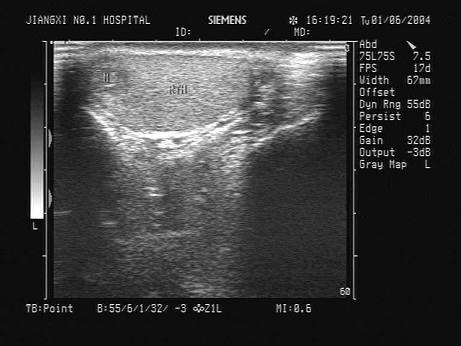

问题 某患者五日前阴囊碰伤,现感右侧阴囊不适,超声声像图如下,最可能的诊断为?(?)

选项 A.睾丸血肿 B.精原细胞瘤 C.睾丸炎 D.睾丸扭转 E.睾丸脓肿

答案 A